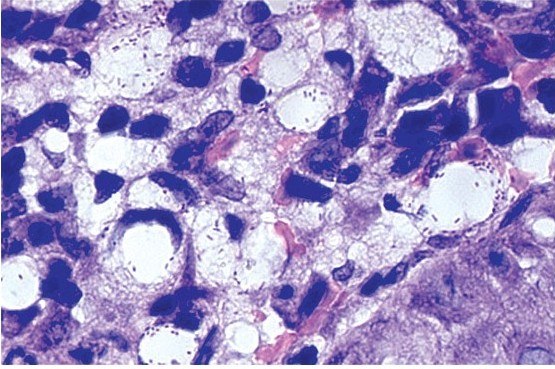

Хронический ринит (насморк) - неспецифический дистрофический процесс слизистой оболочки и в ряде случаев костных стенок полости носа (Денисов, 2003).